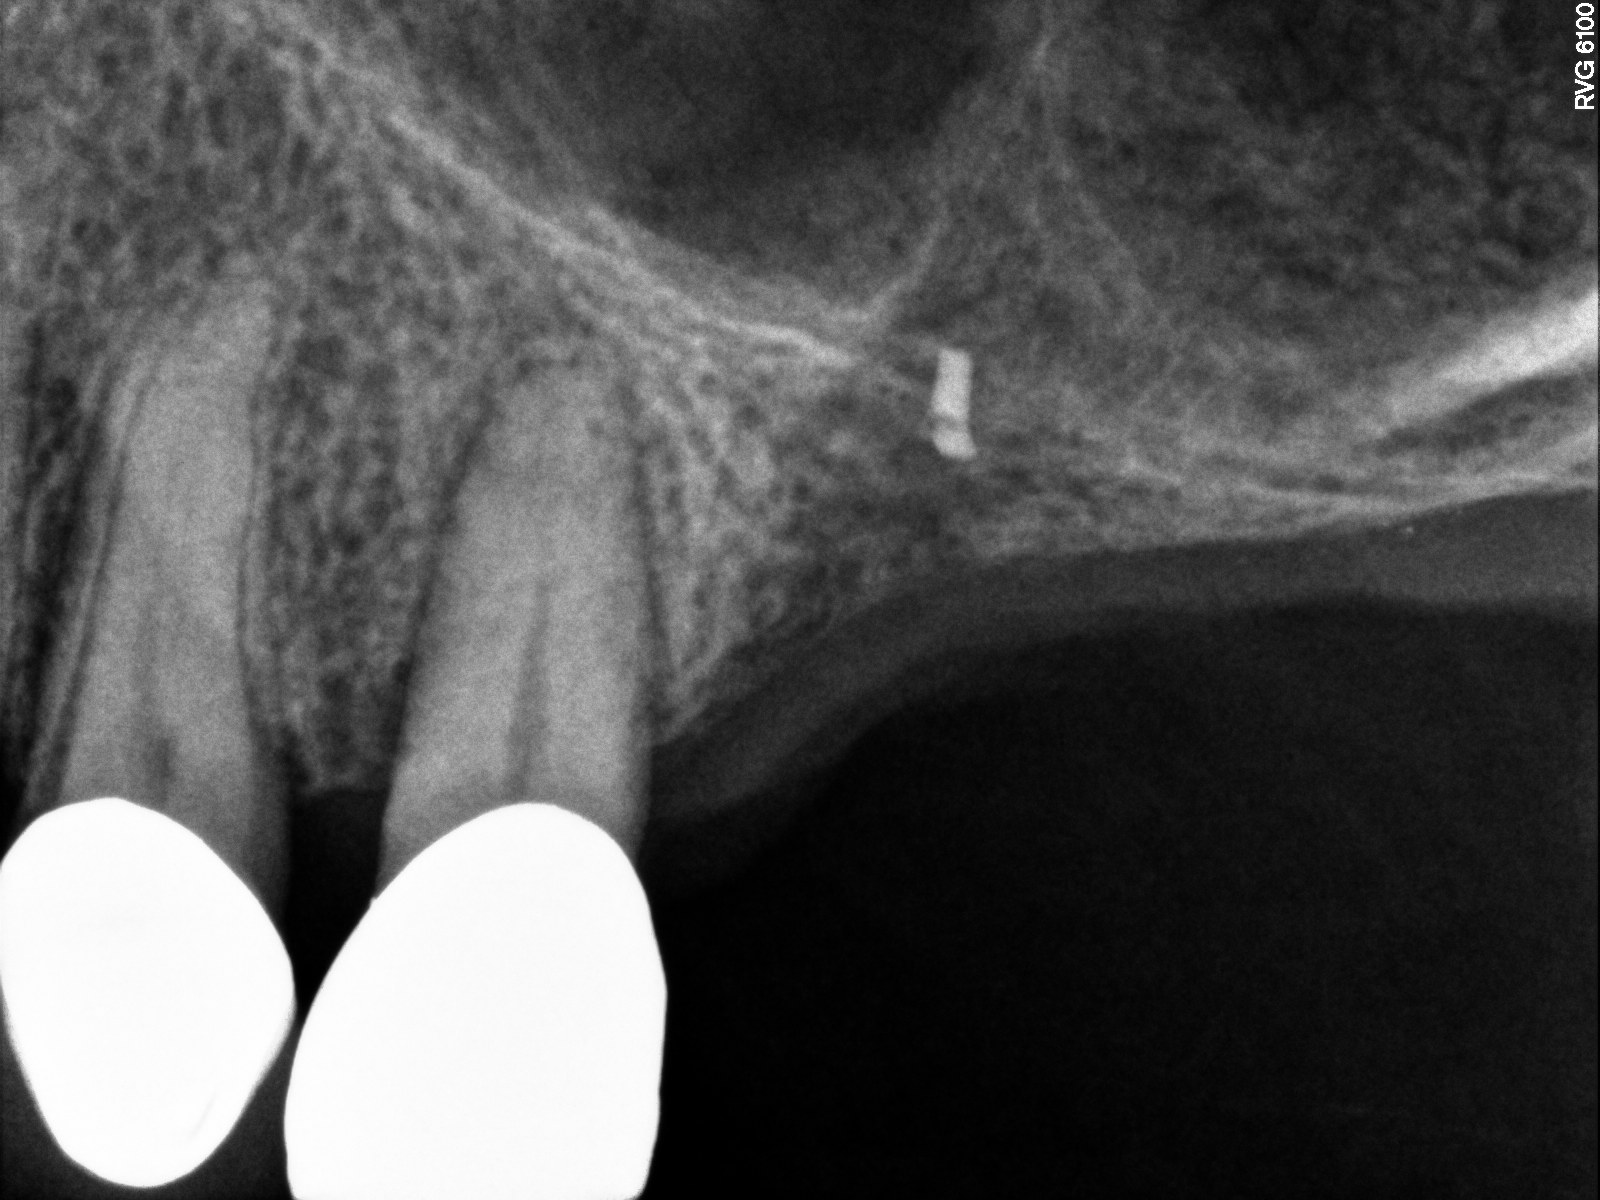

Case 3. Preoperative radiograph showing about 3.5 mm of ridge height.

Fig. 20

This patient was a 73-year-old man with only about 3.5 mm of native bone in the No. 3 site (Figure 20). The composite graft used here was a 50:50 mixture of DFDBA and deproteinized bovine bone mineral (Osteohealth, www.osteohealth.com) with approximately 40% calcium sulfate added. The implant was the same type and length as in Case 1 above. Figure 21 shows the area on the day of placement. In the CBCT scan on the day of placement (Figure 22), the native bone and bone graft were clearly discernable. However, the postoperative radiograph taken at 6.5 months (Figure 23) showed no marginal bone loss and a significantly denser appearance than when the graft was place. The membrane was raised about 7 mm to 8 mm. The final radiograph was taken after extraction of tooth No. 2 and after extraction of tooth No. 4 and immediate implant placement.